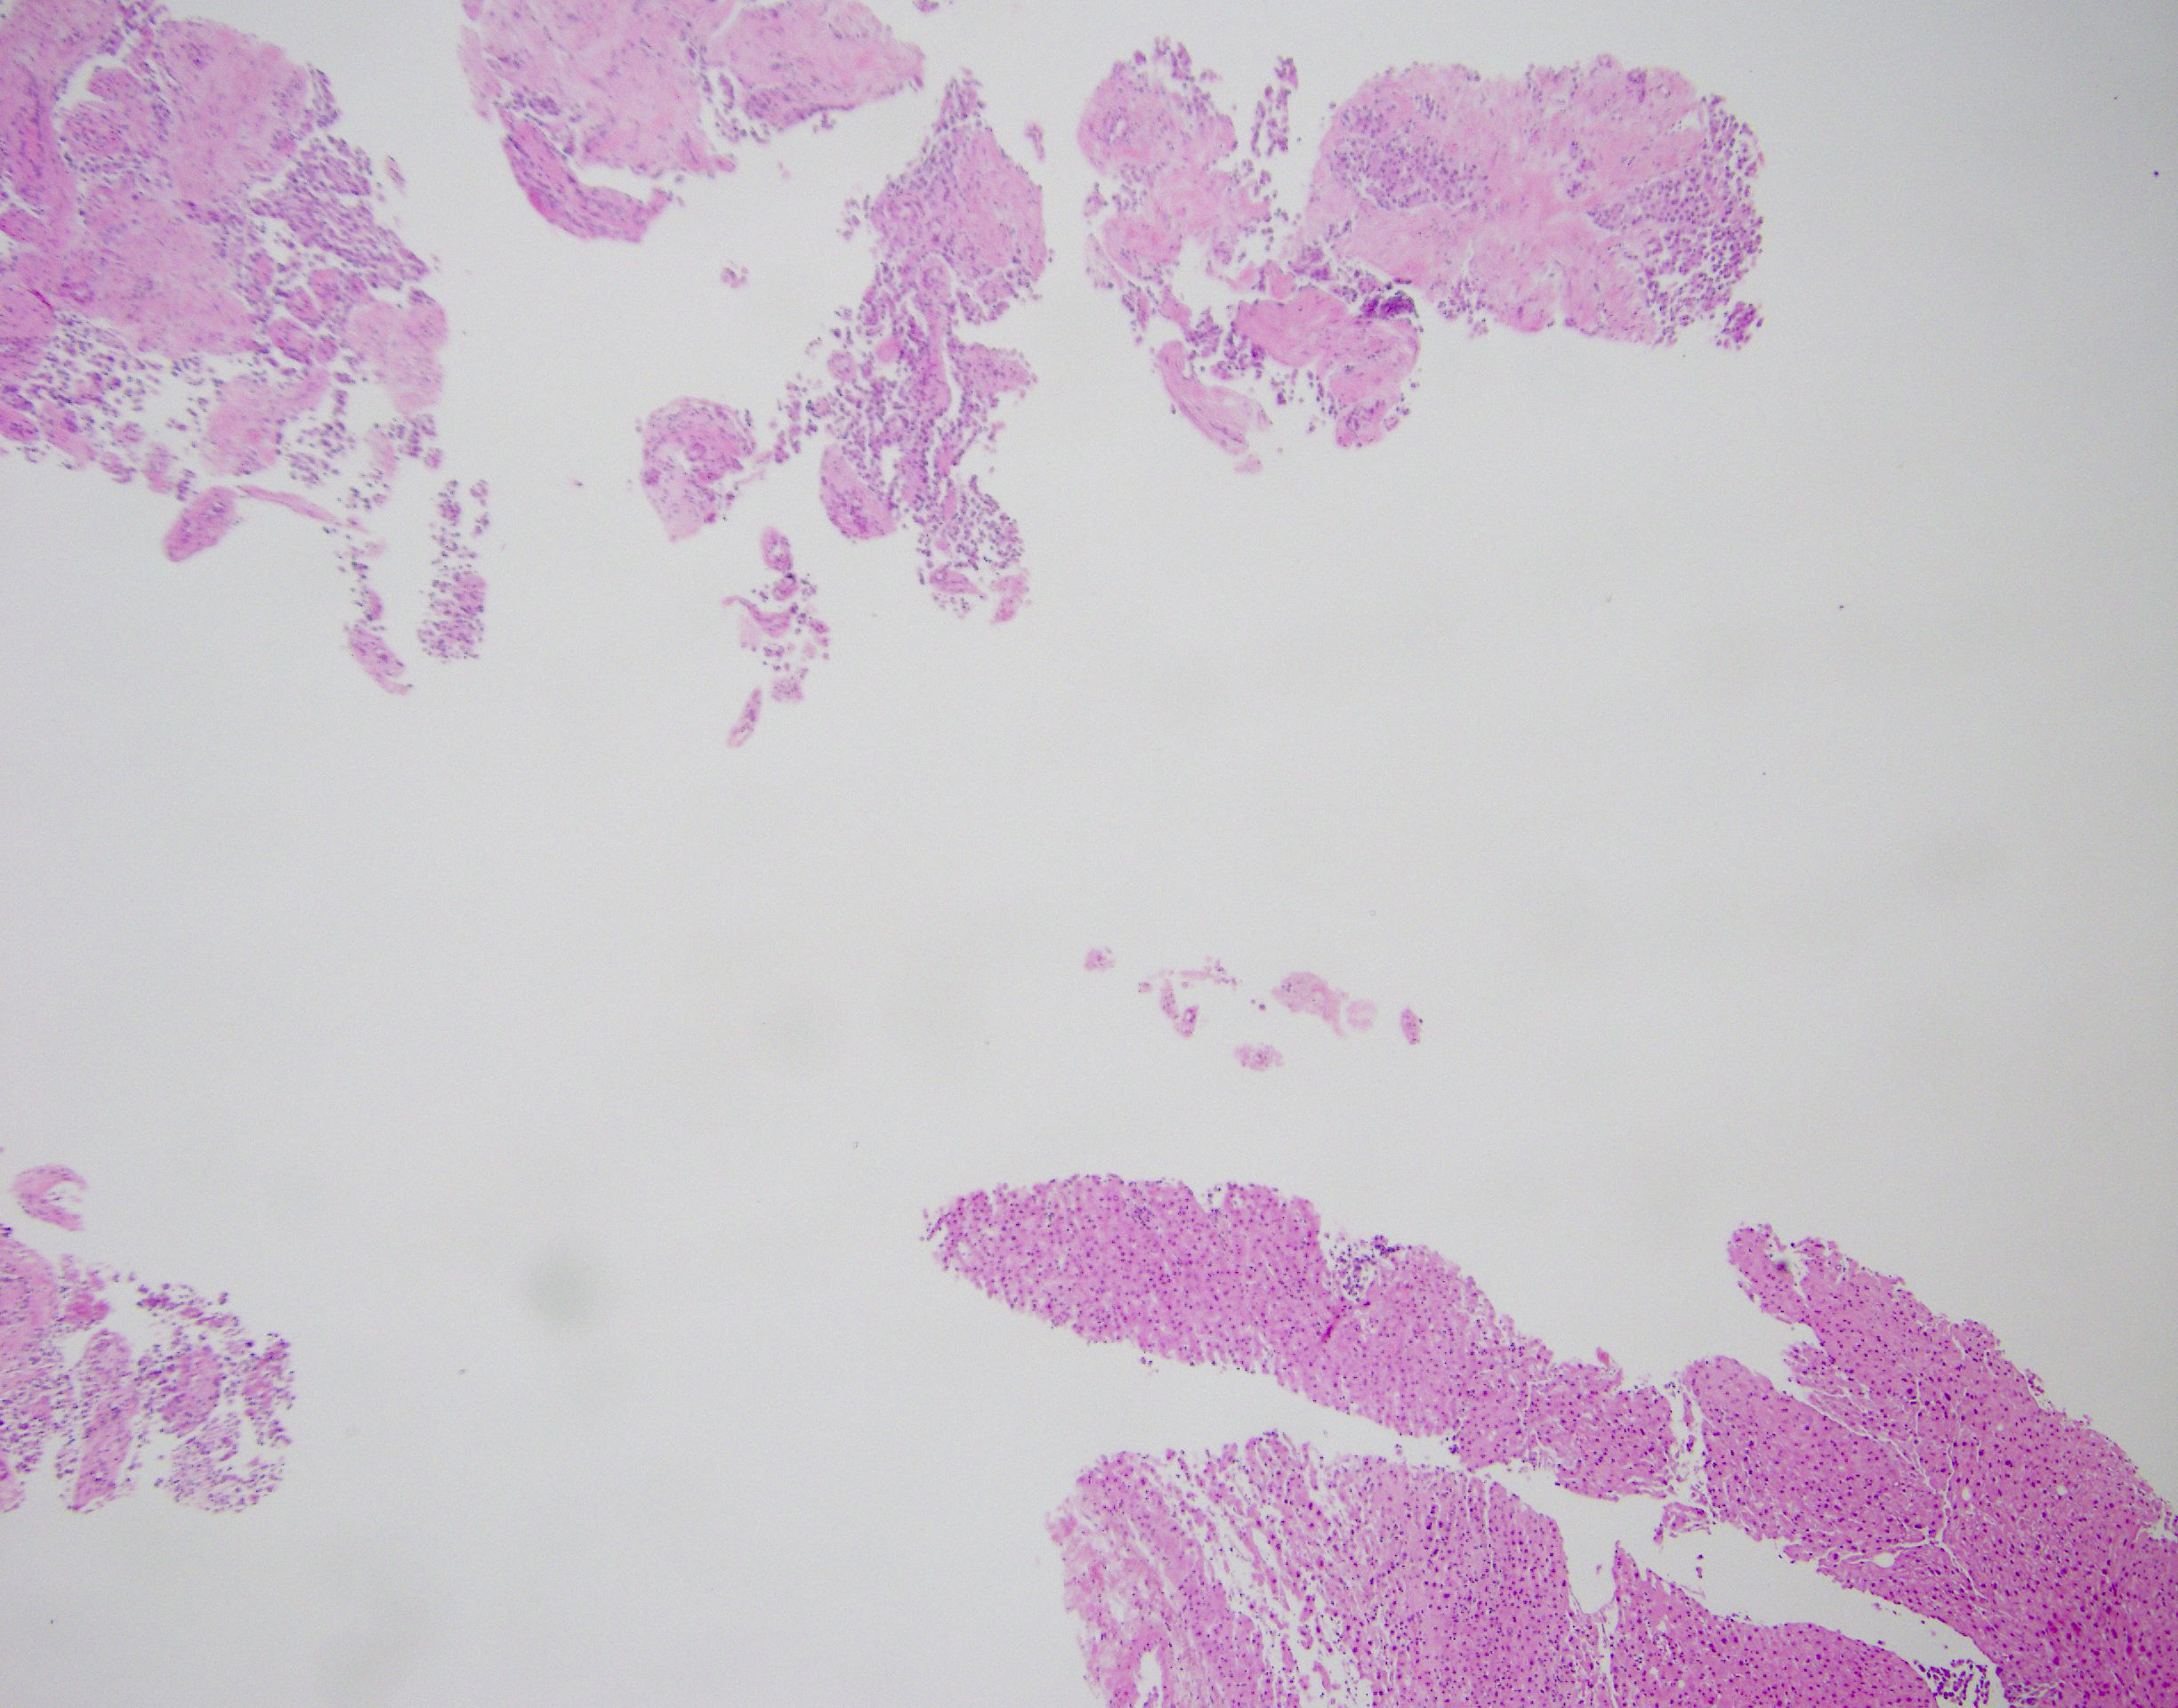

Microscopic (histologic) description

- Tumors are heterogeneous, with variable admixture of solid and pseudopapillary areas

- Solid areas are comprised of uniform cells admixed with capillary sized blood vessels

- Pseudopapillae are formed due to tumor cells getting detached from blood vessels forming fibrovascular stalks or rosette-like structures (Arch Pathol Lab Med 2020;144:829)

- Stroma usually shows various degrees of hyalinization or evidence of degeneration, such as hemorrhage, foamy macrophages, calcification and cholesterol clefts

- Tumor cells usually have a moderate amount of eosinophilic cytoplasm with intracytoplasmic hyaline globules (PAS+ and diastase resistant, positive for alpha-1-antitrypsin) and perinuclear vacuoles (Am J Surg Pathol 2011;35:981)

- Relatively uniform nuclei with finely textured chromatin, inconspicuous nucleoli and characteristic longitudinal grooves

- Variants include clear cell, oncocytic and pleomorphic

- Rare mitotic figures

- Although grossly well circumscribed, microscopic finding of infiltration to the surrounding pancreatic tissue is not uncommon

- Rare cases of highly aggressive behavior; histological features in those cases included diffuse growth pattern, extensive necrosis, significant nuclear atypia, high mitotic count (35 - 70/50 high power fields) or sarcomatoid features (Am J Surg Pathol 2005;29:512)

Microscopic (histologic) images

Contributed by Monika Vyas, M.D., Omid Savari, M.D. and Raul S. Gonzalez, M.D.